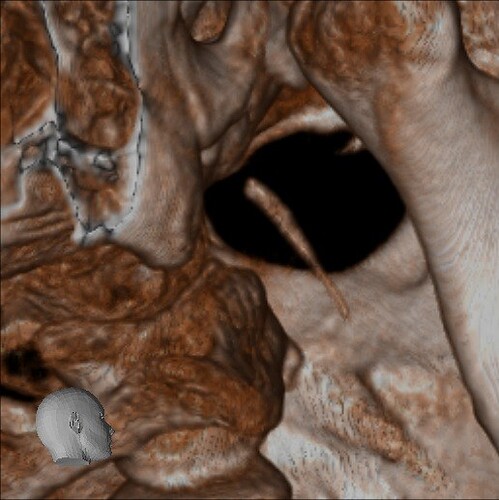

Below are some screenshots from my Cone Beam CT scan and the report linking possible ES. I have more Regular CT scans I could possibly share and/or if you would like me to get possible better angles from the Cone Beam CT scan let me know. But as of right now I’m at a loss as what to do going forward. I do have an MRI with and without contrast of the Cervical Spine Scheduled, but that’s due to the doctor’s (the doctor that dismissed it as ES and one doctor that wants to follow up and learn more on it) wanting it.

- Now onto this year, I finally got better back to full health in late November early December 2024 and sadly started to get another sinus infect in January and still no answers to why. I just happen to be watching YouTube when a Dentist had said that your teeth could be linked to sinus issues causing sinus infections and normally the only way to tell if this is the case is to get a Cone Beam CT scan. I then thought this could be another lead to find out why I keep getting sick as I did when I was 10 have my first top premolar on my left side removed against what I wanted as they said my teeth were too crowded and it needed to be removed so I could have braces (which that dentist didn’t even do my braces anyway). But I thought when he removed it if a small piece of the root was still in there as he just broke out the tooth without removing it via surgical means that that could cause an abscess in my Left Maxillary Sinus where infections always start. So, finally I was able to find a place that would give me a Cone Beam CT scan back in February of this year all while I was just starting to get sick from my infection. Anyway, I finally got the report in March and found out oddly my Left side is mostly normal other than mucus polyps, but I have a few other issues (I have attached the report below). This report is where I first found out about Eagle Syndrome as it states I might have Calcified Ligaments and further testing is needed to confirm. It was only after this report and looking up what Eagle Syndrome was that I can say I have almost every symptom that has ever been reported. Sadly, I couldn’t find anyone in my State at the time that work with Eagle Syndrome and when I did was about a week before I found this site and the doctor I did see seemed to dismiss me as another hypochondriac and you can’t have it as you don’t have Vertigo type Dizziness, my styloid are normal length and I don’t have neck pain equivalent to having to be in a neck brace. Not only this she only looked at my CT scan from a week earlier that I had got in Emergency. The Emergency visit was due to the fact at 8PM that night I had pain in my Right Mastoid Bone, and I was starting to get an earache. I went to lay down and took pain meds and an ice pack in hopes to reduce the pain and swelling. I couldn’t sleep due to the pain and came upfront about 10PM. 10:21PM I couldn’t take it anymore and started to stretch my neck and I felt a huge snap and heard a load pop, all the pain just felt like it disappeared. One minute later, I had a massive pain that spread just like when you get an IV that stings, but it felt like someone was trying to murder me and stabbed a knife into the right side of my skull. I was in so much pain that I was hunched over, and we had to have an ambulance called. I thought I was having an aneurism and my mother thought I was having a Stroke (very rare ES Symptom). When the ambulance arrived, they took my vitals, and my blood pressure was 148/110 with a pulse in the high 90’s low 100’s. Luckily the pain had subsided enough that we were able to go to emergency without the ambulance ride, but while I was in emergency the pain had spread to my left side of my head and now felt like someone had taken a clothes iron and stuck it on my head. Any breeze moving my hair was pure agony and I couldn’t lay my head on a pillow without that burning pain. According to emergency though I must have just had a Mastoid Process infection and it burst. Luckily the pain went away by the time I went to the Doctor for ES, but like I said before they were of no help.